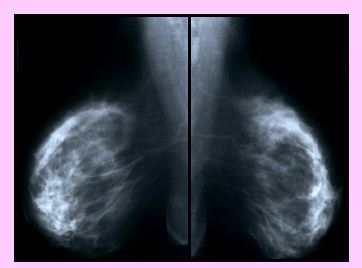

Karcinom prsní žlázy je nejčastějším zhoubným onemocněním

žen

Screening karcinomu prsu České republiky